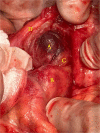

Epiploic appendagitis (EA) is an uncommon condition caused by infarction of epiploic appendages "small fat outpouchings present on the outside of the colon wall" because of torsion or thrombosis of the main draining vein. It is sometimes misdiagnosed as diverticulitis or appendicitis. Lab tests usually are normal, and the diagnosis is mainly by computerized tomography (CT) scan. Treatment is conservative as it is a self-limited condition, and the symptoms will resolve spontaneously within 2 weeks. However, surgical appendage removal could be necessary if symptoms increase or continue. Here, we report our experience with a 21-year-old male patient, who presented with a 1-day duration of localized right lower quadrant (RLQ) abdominal pain within 18*10 cm incisional hernia, imaging revealed signs of epiploic appendages infarction within the huge incisional hernia. This case describes an atypical scenario for EA, which was successfully managed with surgery. The final pathology report confirms the diagnosis.